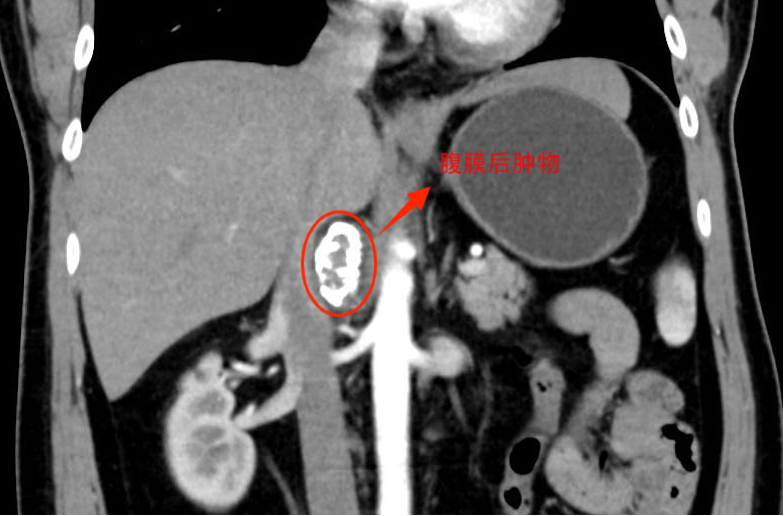

广州市民梁先生(化名)在体检中发现,腹膜后有一个约4厘米的占位,随后被确诊为一种较为罕见的神经内分泌肿瘤——副神经节瘤。虽然多数为良性,但它的特殊性质与所在位置被视为高风险病灶。

“这个位置,用我们外科医生的话说,是‘最不该长肿瘤的地方’之一。”南医三院泌尿外科主任刘存东教授解释。肿瘤被“卡”在了人体最粗的腹主动脉和下腔静脉之间。周围毫米级的狭小空间内,密布着为肠道供血的关键动脉、肾动脉、肾静脉,以及十二指肠、胰腺等重要器官和神经。